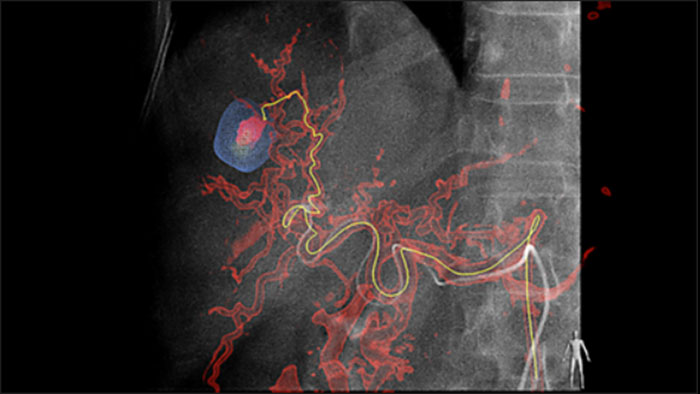

La solución de Detección Automática de vasos Alimentadores puede mejorar significativamente la detección de arterias dependientes. EmboGuide le ayuda a maximizar la eficacia de sus procedimientos TACE, ya que potencialmente mejora su sensibilidad, reduce los falsos positivos y maximiza el acuerdo entre lectores1. EmboGuide también proporciona una guía 3D en vivo eficiente y basada en el flujo de trabajo con detección automática de vasos alimentadores1.

La adopción de técnicas de quimio/radioembolización como TACE y SIRT impulsa la necesidad de estandarización y eficiencia. Caso tras caso, debe localizar de manera confiable y consistente los tumores, identificar todos los vasos dependientes y planificar /ejecutar el enfoque intervencionista apropiado. Nuestra solución de Detección Automática de vasos Alimentadores puede mejorar significativamente la detección de arterias dependientes en comparación con el uso de CT de haz cónico solo. EmboGuide le ayuda a maximizar la eficacia de sus procedimientos TACE, ya que potencialmente mejora su sensibilidad, reduce los falsos positivos y maximiza el acuerdo entre lectores.1

La capacidad de detectar y de distinguir nódulos hepáticos e identificar los recipientes minúsculos del vaso alimentador es crítica para determinar terapia apropiada. Navegar a la región de interés llegando a todos los vasos alimentadores, sin dejar de ser selectivo con la lesión, aumenta la oportunidad de éxito. La confirmación del criterio de valoración del tratamiento y el éxito del mismo mientras el paciente todavía está sobre la mesa aumenta la confianza en los resultados clínicos.